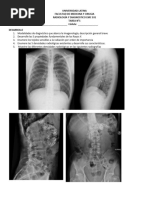

DENSIDAD Y ESCALA DE GRISES

Unidades Hounsfield

Escala cuantitativa utilizada

para describir los

diferentes niveles de

radiodensidad de los tejidos

humanos.

VENTANA

Conjunto de valores de la gama de

densidades que se muestra en la pantalla

del monitor que mejora la visibilidad de

las estructuras.